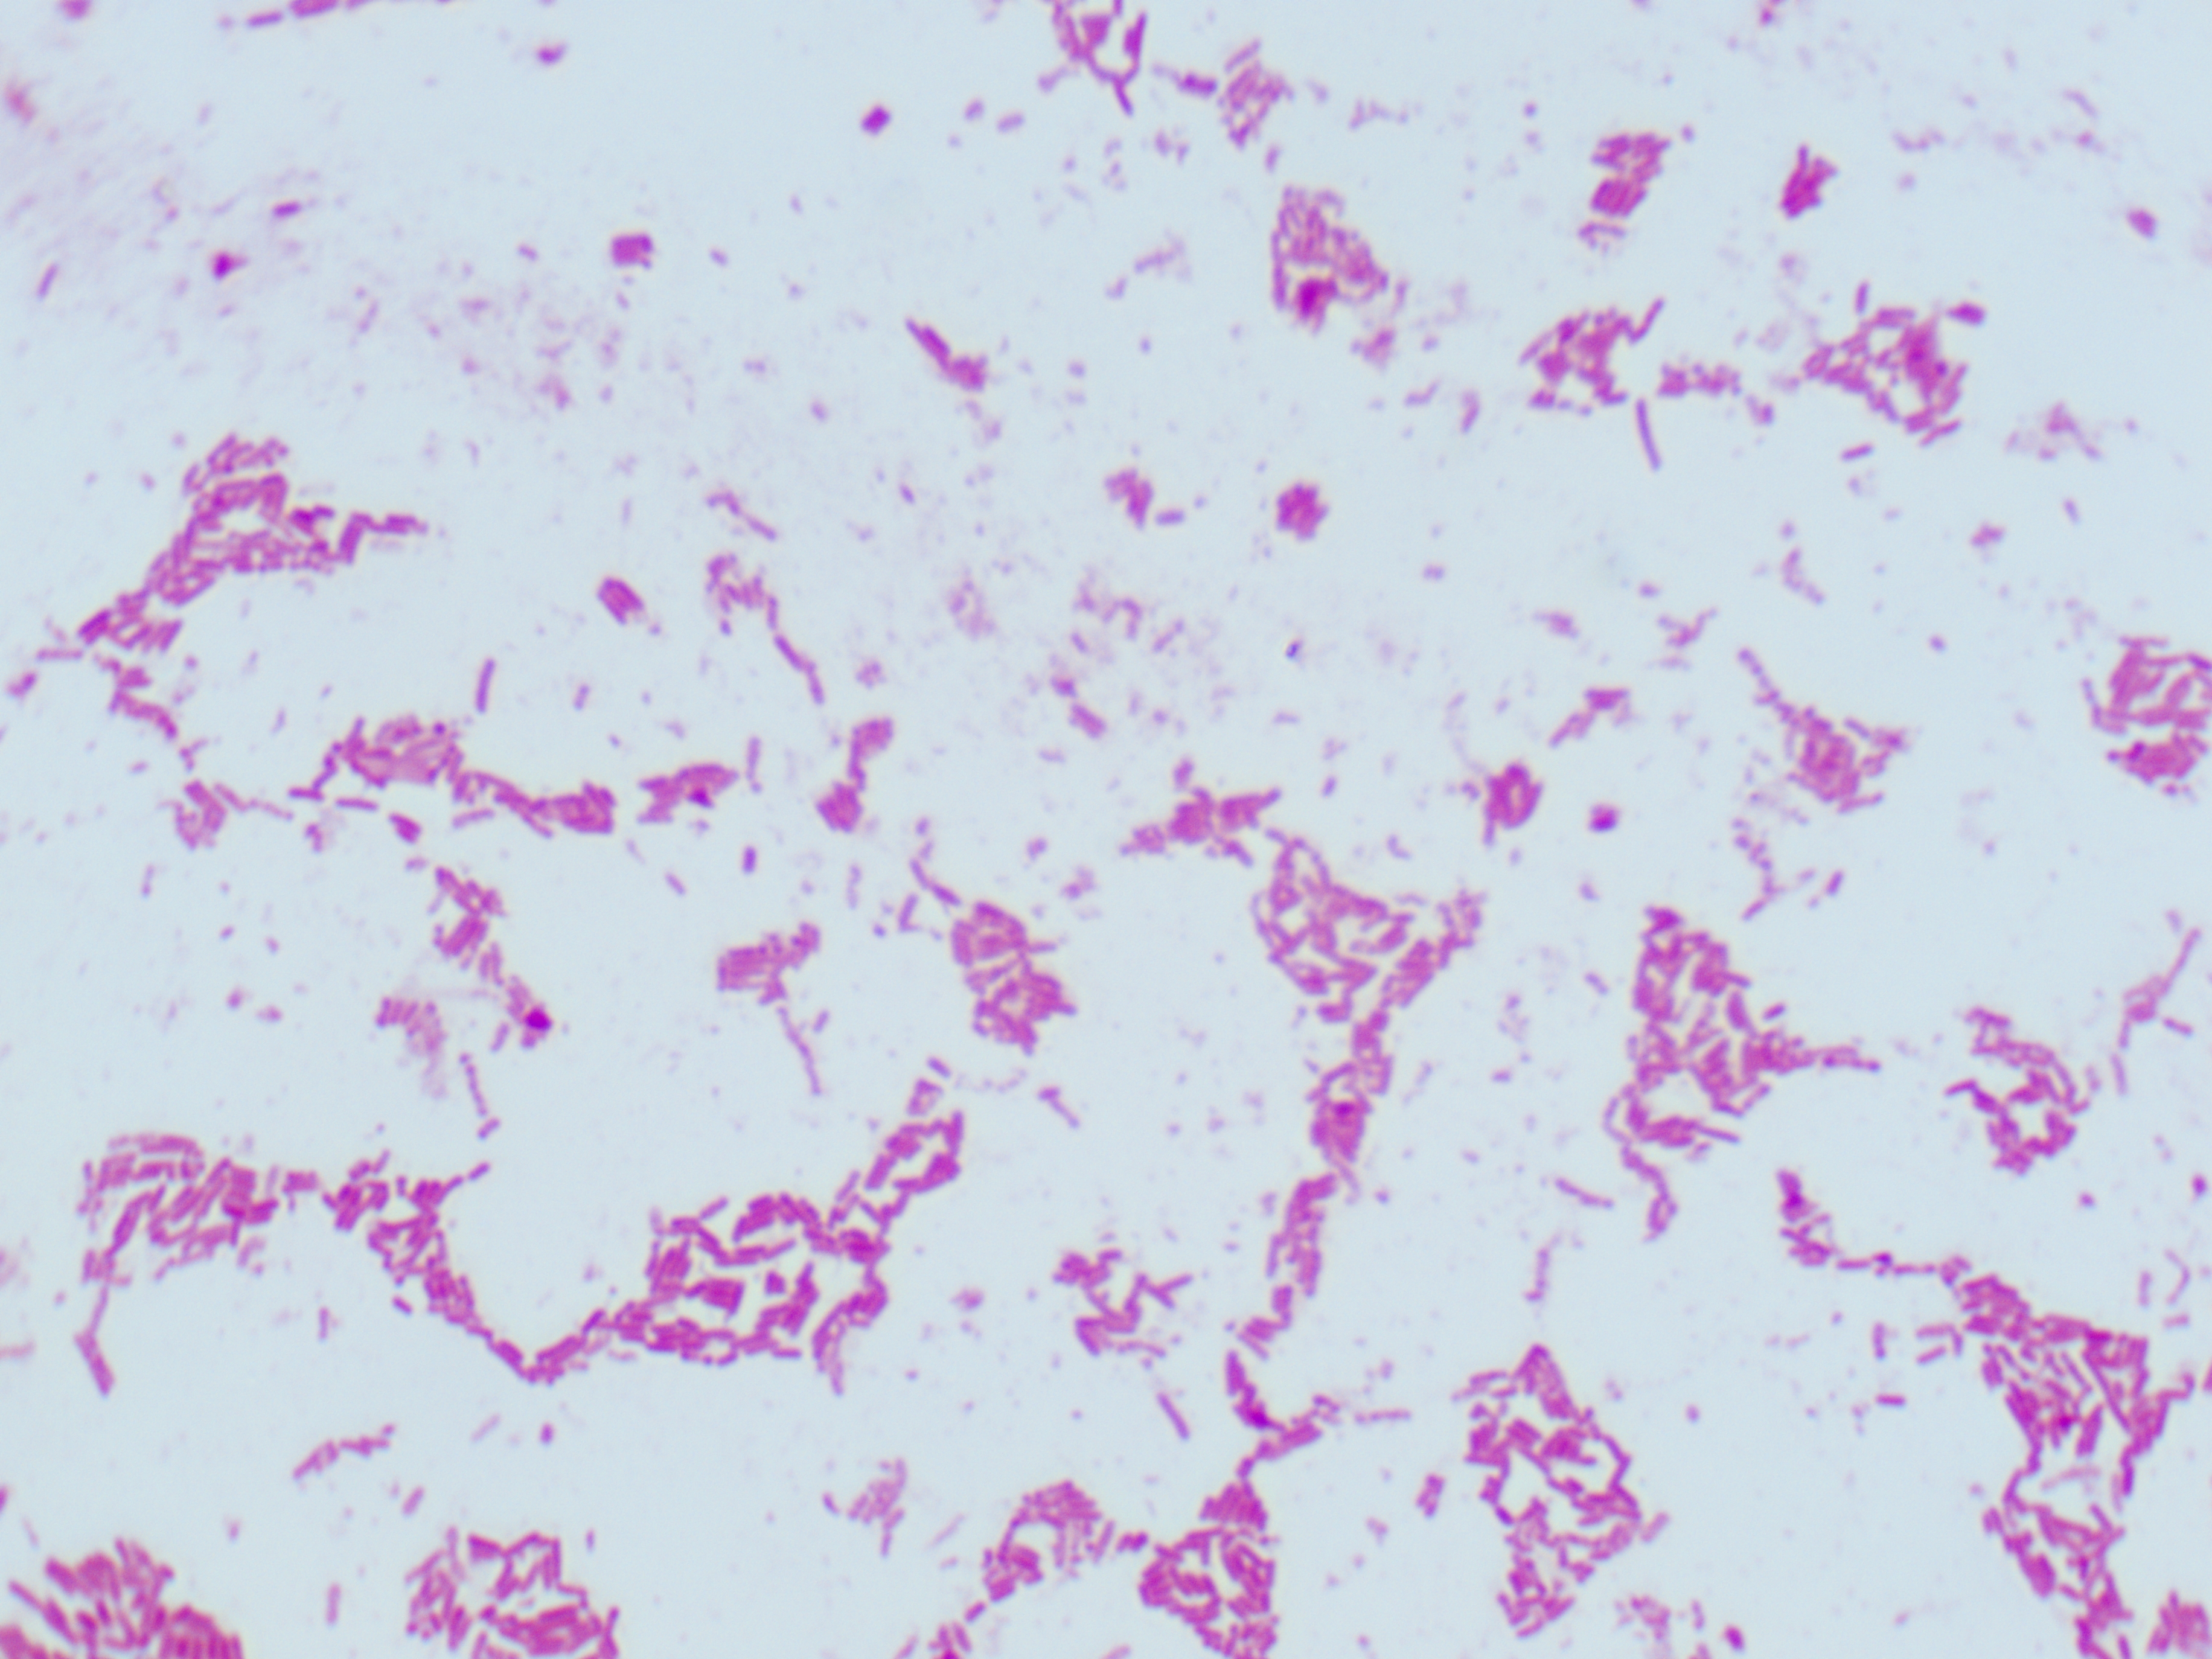

- Pathological Microscopy Data – Gram stain, Methyl blue stain, and more.

Deep specialization in radiology, pathology, and histopathology datasets, annotated with medical precision.

Healthcare & Medical Data Supply

We specialize in healthcare datasets including radiology (CT, X-ray, MRI, Ultrasound, Echocardiography), pathology microscopy, and histopathology images — all ethically sourced and research-ready.

- Pathogen